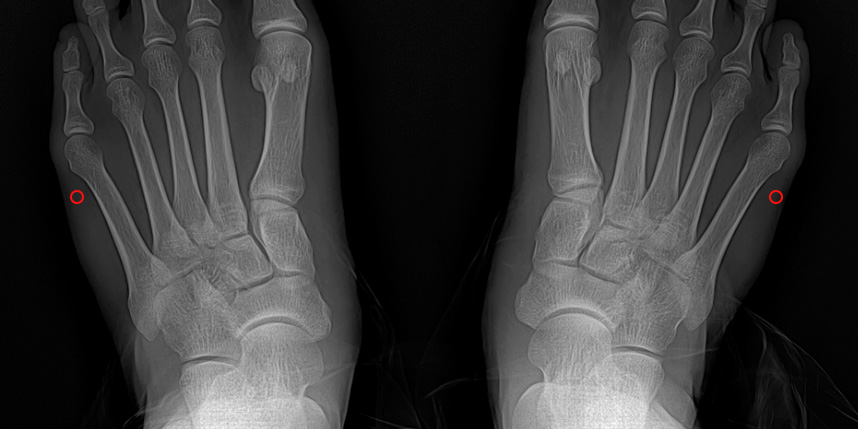

소건막류는 새끼발가락 관절의 뿌리 부분이 바깥쪽으로 튀어나오면서 발생하는 변형입니다.

소건막류의 원인은 다양하지만

가장 흔한 원인은 유전적인 요인입니다. 가족 중에 소건막류가 있는 경우 발병 가능성이 높아집니다.

굽이 높거나 폭이 좁은 신발을 자주 착용하는 것도 소건막류의 원인이 될 수 있습니다.

이외에도 평발, 류마티스 관절염, 외상 등이 소건막류의 원인이 될 수 있습니다.